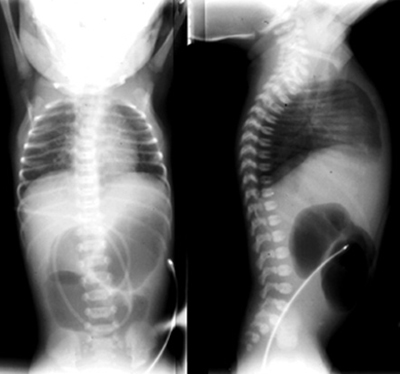

Duodenal Atresia

The most common cause of congenital duodenal obstruction is duodenal atresia. Failure of recannulation of the duodenum typically occurs in the region of the ampulla of Vater. It is often diagnosed prenatally on OB ultrasound. The incidence is 1 in 10,000 live births. Associated disorders include Down syndrome (30%), malrotation (20%), heart disease (20%), renal anomalies, tracheoesophageal fistula, and the VACTERL anomalies. Symptoms include bilious vomiting in the first day of life. Treatment is surgery. |